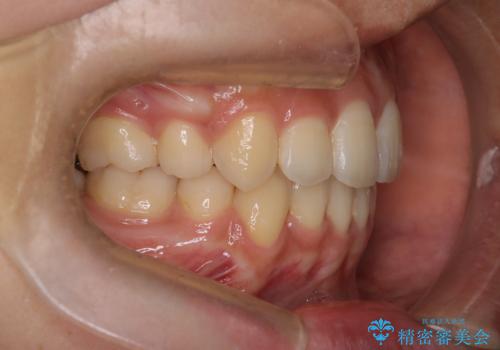

- 八重歯を主訴に来院されました。4番の歯を4本抜歯し、八重歯を並べる計画をたてました。

抜歯をし、スペースを確保したことにより八重歯をきれいに並べることが出来ました。